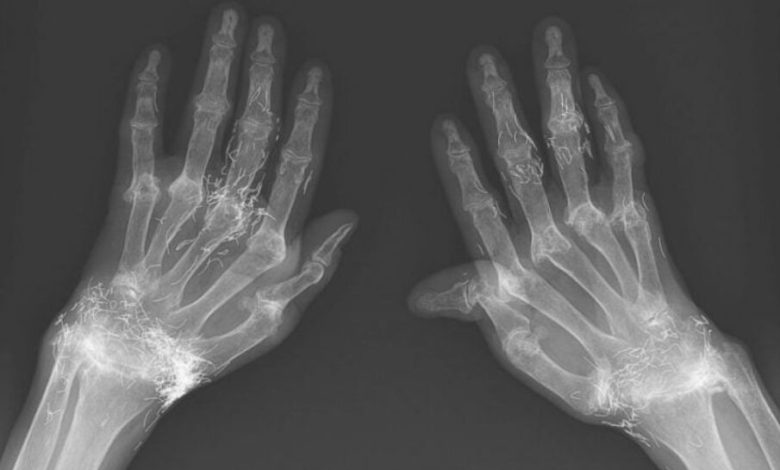

اما این روش هم نهتنها دردی از این زن دوا نکرد، بلکه زانودرد او را هم شدت بخشید. درنهایت او مجبور شد دوباره به بیمارستان مراجعه کند و پزشکان هنگام تصویربرداری از زانوها و دستهای او متوجه صدها رشته ریز و نازک از طلا در بافتهای اطراف زانو و دستهای این زن شدند.

طب سوزنی با رشتههای طلا در برخی از کشورهای آسیایی، بهویژه میان سالمندان، رایج است اما پزشکان هشدار دادند این روش هیچ پشتوانه علمی ندارد و حتی ممکن است موجب عوارض خطرناکی چون ایجاد کیست، جابهجایی نخها در بدن، آسیب به بافتها و حتی اشکال در انجام تصویربرداری MRI شود.